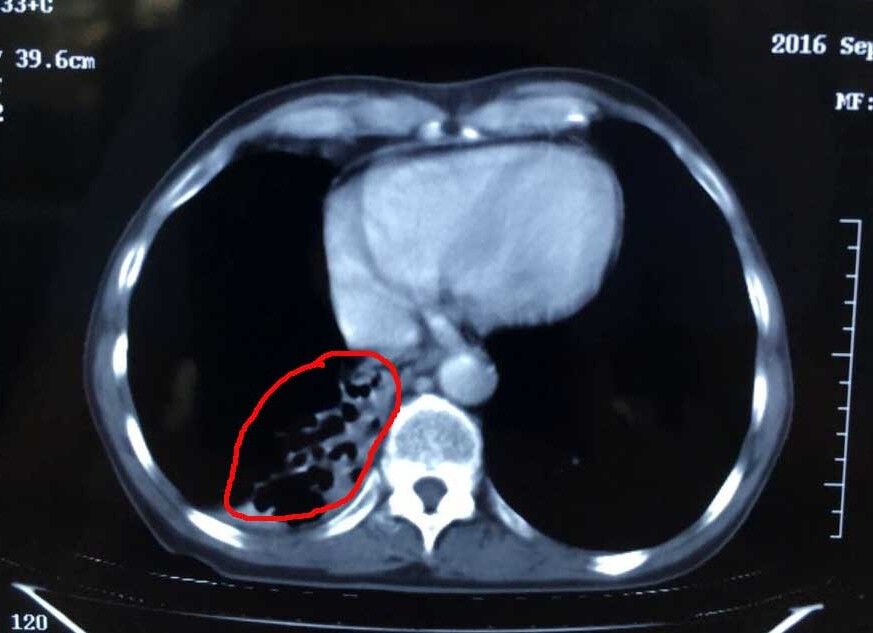

肿瘤治疗后

术前的杨清贵心情十分忐忑,但听了医生一番话后又恢复了平静。“林菁医生耐心地跟我们解释了治疗有哪些风险,如肿瘤靠近肺门以及气管,冷冻治疗可能会造成出血、咳血、气胸等,但很快又给我们服下定心丸,‘医院每天都做5-6台这样的手术,手术的专家经验都十分丰富,出现并发症的情况极少。’”张英友说道。据了解,经过近3个月的综合治疗,目前杨清贵的肿瘤几乎全部消失,胃口、睡眠等恢复良好,身体与常人无异。